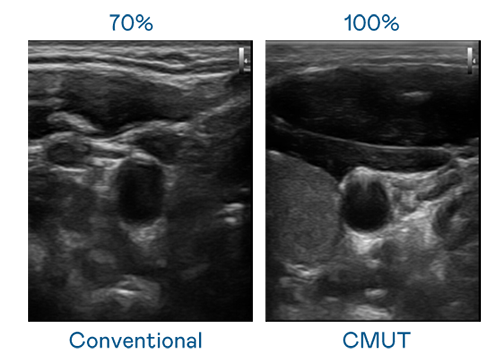

CMUT 技术是一种用电容式微机电元件来产生超音波讯号的技术。与传统 PZT 压电式技术相比,CMUT 频宽增加 30%,更宽频的超音波讯号让影像解析度大幅提升,是实现高影像品质医疗超音波扫描、促进精准医疗发展的关键技术。

超音波影像的解析度高低,首先取决于探头能发出的讯号频宽。银河galaxy CMUT 可提供高清晰的超音波讯号,提供高频宽、高灵敏度、影像纹理细节更高的超音波影像,协助医护人员缩短影像判读时间及利用精准的医疗影像进行诊断。